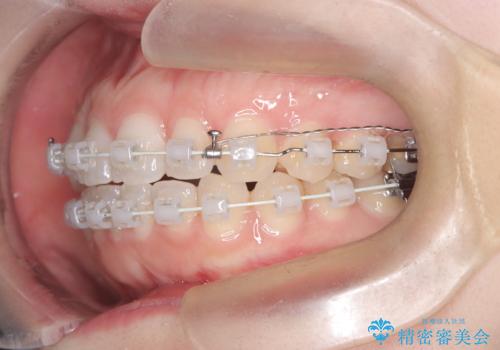

今回の矯正では、装置が目立たないよう透明なブラケットと白いワイヤーを使用。さらに、効率的な歯の移動のために、歯の裏側にリンガルアーチを設置しました。また、確実な奥歯の移動のために**TAD(矯正用アンカースクリュー)**を一時的に使用。これにより、犬歯を狙った位置へ正確に動かすことが可能に。目立ちにくい装置で快適に過ごしながら、理想的な歯並びと咬み合わせを獲得していただけました。